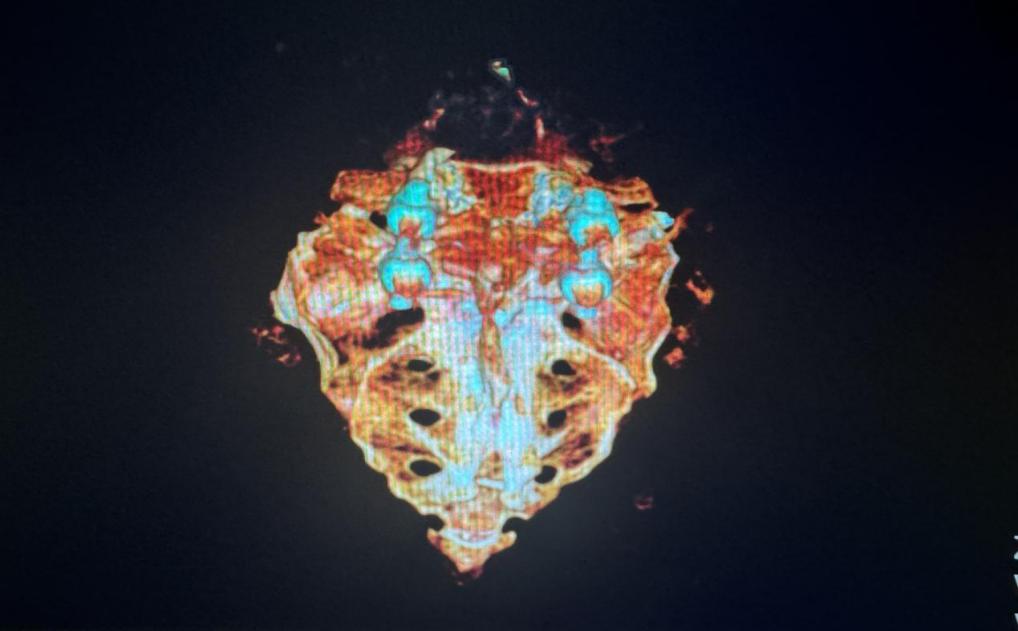

患者入院后,西安交通大学第二附属医院副院长种铁教授带领陈琦副主任医师、南宁主治医师等医护团队,就患者病情分析讨论,从既往病史与系统检查确定了诊断及病情,就患者骶骨三维重建提示骶骨发育异常、S1椎板融合不全并V型隐裂,合并糖尿病多年且继发腰骶部复合损伤,多种因素导致腰骶神经系统损伤后神经源性膀胱肠道功能障碍,制定了规范、系统与长期的诊疗方案;同时,考虑患者未来不能避免全身及局部磁共振检查可能性,经与患者及其家人充分交谈、病情告知并征得同意,泌尿外科“尿控与盆底修复”团队于5月22日13时,为患者实施了西部首例磁共振兼容-骶神经调控Stage 1手术治疗。

骶骨三维重建 超声引导下定位